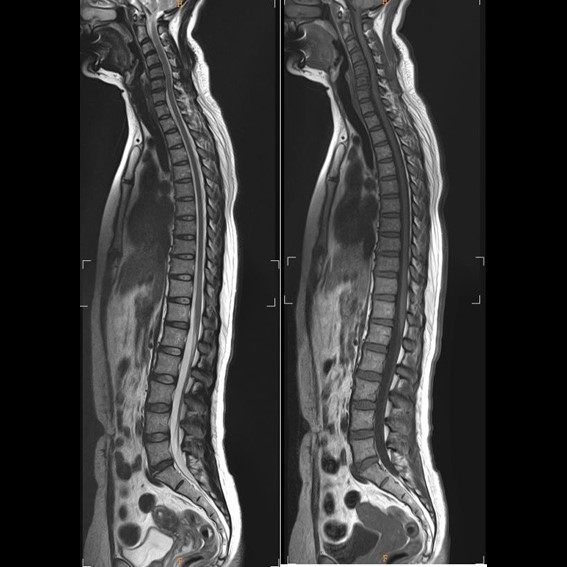

運用高科技尖端影像設備,提供貴賓精準的檢查、判讀、即時醫療、後續追蹤、健康管理或醫學中心轉介服務;從健檢診斷到後端治療,一條龍式服務。永越自成立以來,已服務超過16萬人次,每年通報件數超過千件,揪出包括:甲狀腺癌、肝腫瘤、肺癌、乳癌、子宮頸癌等重大異常的健康警訊,把握住早發現早治療的黃金關鍵。